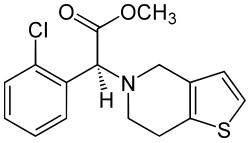

Die Hemmung der Entstehung weiterer Blutgerinnsel, die Thromboseprophylaxe, ist die zweite wichtige Säule der FATE-Behandlung. Sie sollte möglichst früh erfolgen.[33] Hierzu werden zunächst Mittel zur Hemmung der Blutgerinnung wie niedermolekulare Heparine, parallel dazu Mittel zur Verhinderung der Zusammenballung der Blutplättchen (Thrombozytenaggregation) wie ASS und Clopidogrel eingesetzt.[40] Zur Langzeitprophylaxe wird vorzugsweise Clopidogrel verabreicht, da es die Überlebenszeit gegenüber ASS deutlich verlängert.[34][41] Eine Studie aus dem Jahr 2021 konnte zeigen, dass die Kombination von Clopidogrel und Rivaroxaban die effektivste Rezidivprophylaxe darstellt.[42]